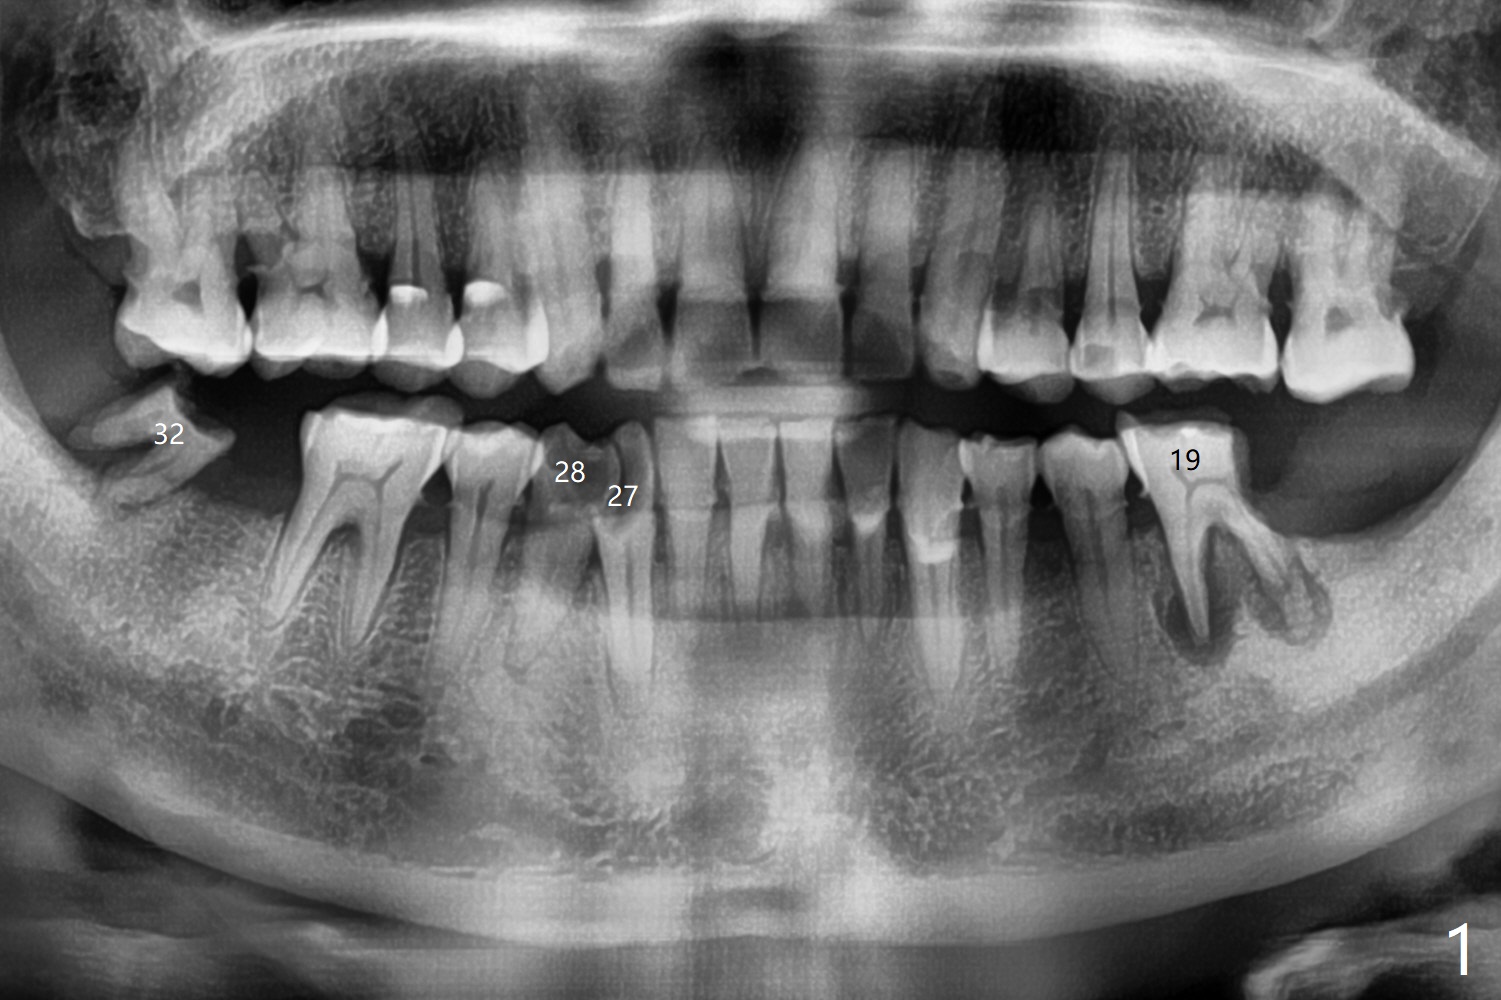

66岁男1.5年前来诊所拍摄全景片(图一),似乎27,28号牙还能保留,今天突然回来,主诉27、28区疼痛瘘道,商量决定先拔除27,28,32及右下深洗。拔除32号牙时发现它接近31区(将要植牙),必须植骨(近中部分(远中塞入胶原塞)),27,28颊侧骨板缺失(大量肉芽组织),植骨理所应当,而且必须拼命推压,但愿推到颊侧骨板,细的皮质骨没有压制感,非要加入粗的松质骨皮质骨,一张12x12毫米胎盘膜剪成两片覆盖27/28和32拔牙窝,4-0 PGA缝线固定,拍摄术后半侧全景片后(图二 (*:骨粉)),使用牙周敷料保护伤口。术后一个月27,28号牙位骨粉保持原位,而且颊侧骨板好像已经重建(图八,十一,九),似乎能植入两个植体(图十,十二)。

Since the distal crest is low at #19 after extraction (Fig.3), a 4.5x11 mm FC implant (Fig.4 green) will be immediately placed in the mesial socket (lingual), which has more clearance from the Inferior Alveolar Canal (yellow). Sticky bone will be initially up to the implant plateau, followed by insertion of a cemented abutment (pink), placement of the 2nd round of bone graft (red) and fabrication of an immediate provisional (white). To save time, a piece of collagen plug is inserted into the apical portion of the distal socket (blue). The distal crest will be expected to increase ~ 3 mm by the procedure mentioned above. The #32 socket heals with apparent exposure of collagen plug 2 weeks postop (Fig.5). The #27 and 28 sockets heal with fresh granulation tissue 2 weeks postop (Fig.6). The fistula buccal to #28 socket appears to have shrunken 2 weeks postop (Fig.7).